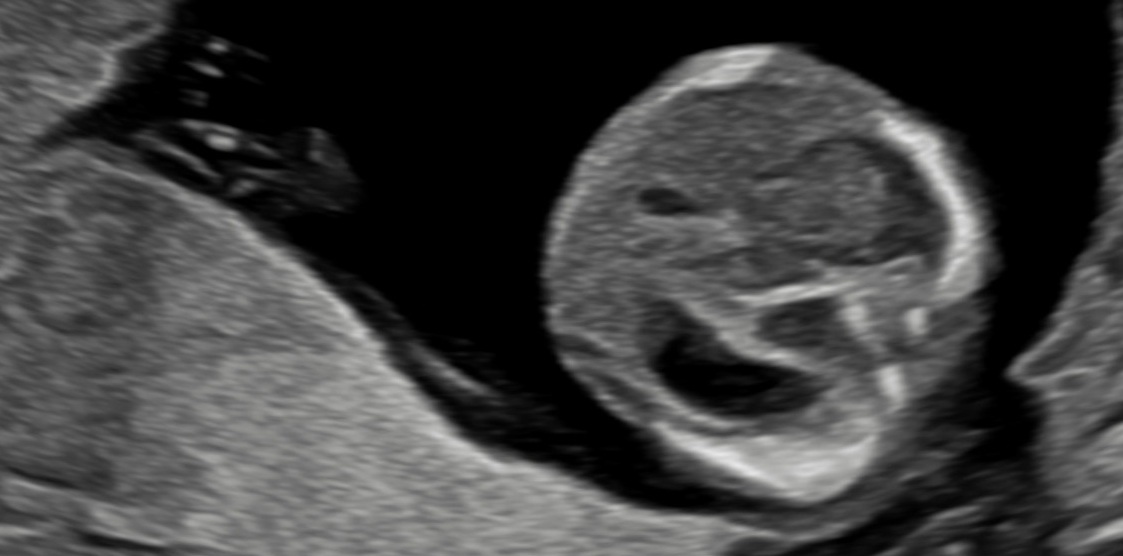

Ersttrimester-Screening: 12-13 SSW

In diesem detaillierten Ultraschall können wir neben der Nackentransparenz bereits die vollständig angelegten Organe Ihres Kindes untersuchen. So erhalten Sie schon früh einen bildlichen Eindruck der ersten Entwicklungsschritte.